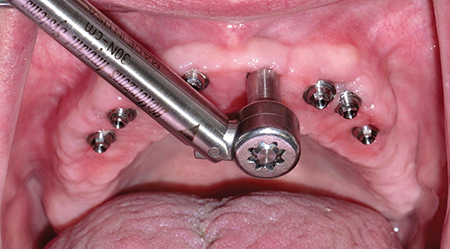

Dentsply Sirona’s integrated solutions for implant dentistry enable dental professionals to deliver safer and more efficient treatment processes as well as increased comfort and improved quality of life for their patients. The merger between DENTSPLY and Sirona has brought together two companies with long-term expertise in their respective fields, providing innovative and clinically tested technology, … Read more